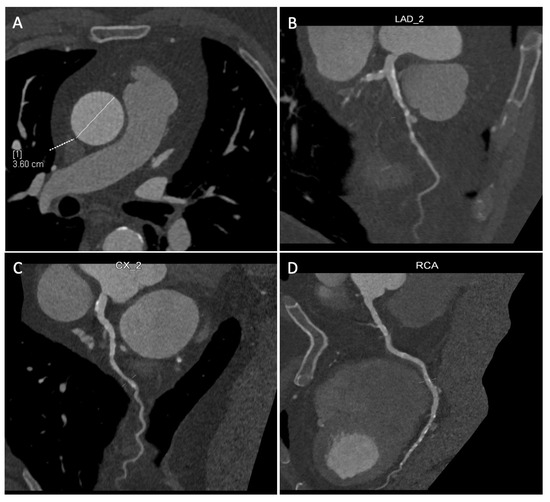

- Absence of calcification of the ascending aorta, allowing the execution of the proximal anastomosis (Figure 4A).

2.3. Preoperative Planning